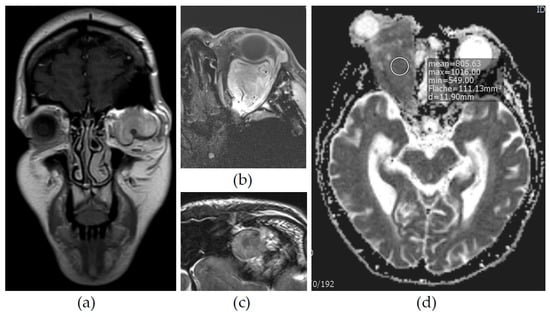

3.2. Imaging

| Patient N° | CT Native ″ | T1 Native (SI) ″ | T2 (SI) ″ | CSA * | ADC ^ | T1 CE | Morphology |

|---|---|---|---|---|---|---|---|

| 1 | n.a. | Hypointense | Intermediate | + | No reduction | Homogeneous | Vessels, well circumscribed, no compression |

| 2 | Hyperdense | Hypointense | Intermediate | + | Artifact | Homogeneous | Vessels, well circumscribed, compression signs |

| 3 | n.a. | Hypointense | Hypointense | − | - | Homogeneous | Vessels, well circumscribed, no compression |

| 4 | Hyperdense | Hypointense | Hyperintense | − | - | Homogeneous | No vessels, well circumscribed, infiltration in parasinuses |

| 5 | Hyperdense | Hypointense | Intermediate | − | Reduction | Homogeneous | Vessels, well circumscribed, compression signs |

| 6 | n.a. | Hypointense | Hypointense | − | Reduction | Inhomogeneous | Vessels, well circumscribed, no compression |

| 7 | Hyperdense | Hypointense | Intermediate | − | Reduction | Inhomogeneous | Few vessels, inhomogeneous intratumoral lesions, compression signs, suspicion of osseous infiltration |

| 8 | Hyperdense | Hypointense | Intermediate | + | Artifact | Homogeneous | Vessels, well circumscribed, no compression |

| 9 | Hyperdense | Hypointense | Intermediate | − | Reduction | Inhomogeneous | No vessels, well circumscribed, inhomogeneous, no compression |